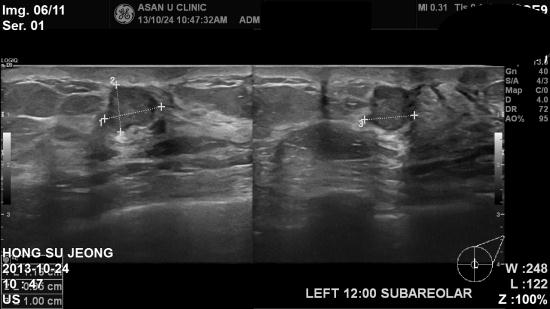

본원 초음파상 좌측유방에

1.16 cm 혹이있어 조직검사

시행하여

침윤성 유방암으로

진단되었습니다.